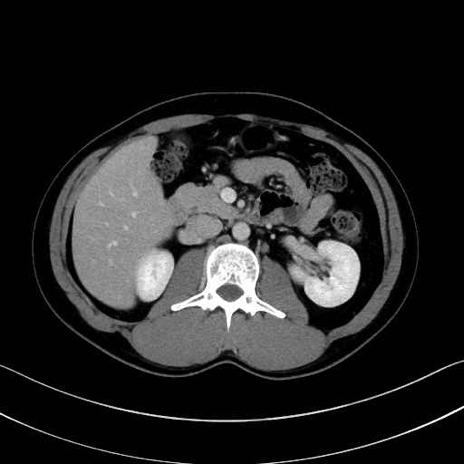

【症例】20歳代 男性 スクリーニング

■起始:脾門で脾静脈枝が合流して本幹を形成。

■走行:膵体尾部の後面溝を右走し、膵頸部の後方で上腸間膜静脈(SMV)と合流して門脈を形成。

■主な流入枝:短胃静脈・左胃大網静脈・膵静脈、そして下腸間膜静脈(IMV)(変異あり)。